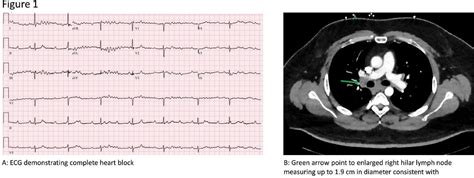

Helen Keith Blog